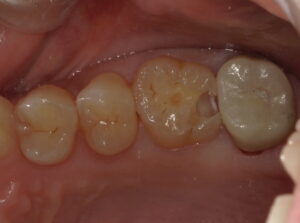

患者さんは30代女性。症状は特にありませんが、定期健診で来ていただいた時に直感で左上6番目の遠心が何となく怪しいと感じました。写真からはほぼわかりません。

詰め物を外してから青い液で染め出したらけっこう中で広がっていました。

虫歯を全て除去しました。神経近くまで広がっていました。